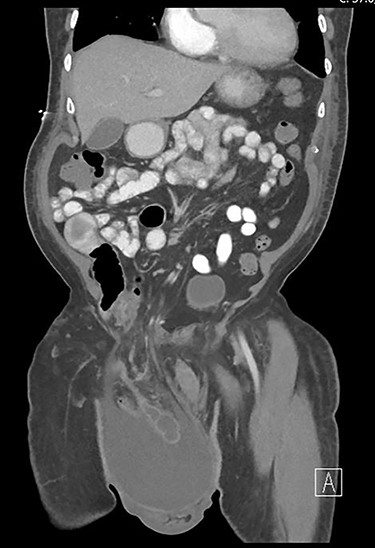

Physical examination revealed a soft, non-tender abdomen and a large, soft, non-tender right inguinal hernia extending into the right hemiscrotum. Lab work demonstrated mild leukocytosis (12 500/μl). Computed tomography (CT) of the abdomen and pelvis showed a large indirect inguinal hernia, containing a large amount of simple fluid as well as the cecum and a non-perforated appendix. There were no signs of bowel incarceration. Notably, the appendix was dilated to 2.9 cm (Fig. 1).

Coronal view of the pre-operative abdominal CT. The appendix was incarcerated inside the inguinal hernia and surrounded by a large amount of simple fluid.

Pre-operatively, our patient’s CT imaging (Fig. 1) proved useful in identifying the Amyand’s hernia and in planning an appendectomy simultaneous with hernia repair. Although, a large proportion of Amyand’s hernias are found during appendectomy, pre-operative diagnoses have been previously reported [3, 4]. In addition to the incarcerated appendix, the large fluid collection in his remarkable abdominal CT imaging was concerning for an inflammatory process. The inflammation was relevant to the categorization and potential management of the Amyand’s hernia [5], as signs of appendicitis would escalate an Amyand’s hernia to a Type 2. This type unsurprisingly carries a higher risk of infection and therefore advices caution when considering a repair with a mesh [5]. However, for our patient, since the size of the hernia was worrisome for promptly recurrence, we decided on the use of an acellular mesh to decrease the risk of recurrence while minimizing the risk of infection.

Further relevant to Amyand’s categorization, the CT imaging and physical examination showed no signs of perforation, peritonitis, or other abnormal pathology; therefore, the Amyand’s hernia was not pre-operatively escalated to either a Type 3 or Type 4. However, as there was no available recent CT imaging, it was considered that the fluid collection and potential inflammation may have been masking another pathology process [4].